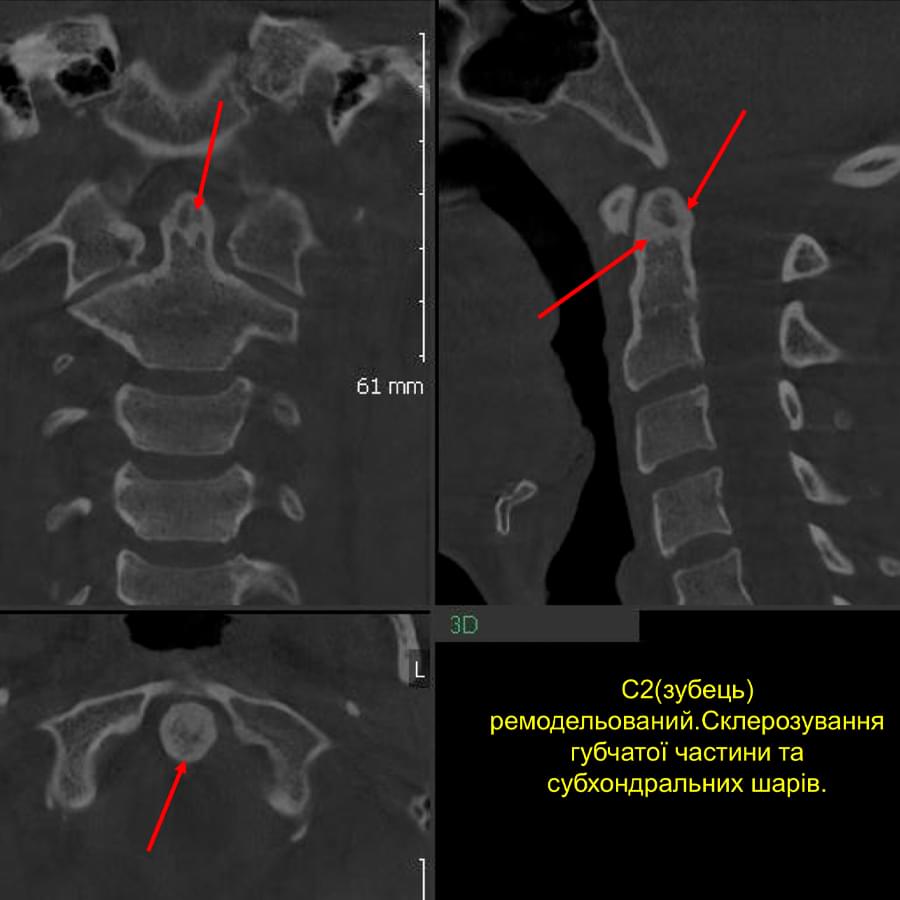

3D цефалометричний аналіз є сучасною технологією, яка дозволяє отримувати точніші,

комплексніші та надійніші дані про зубну та скелетну структуру. Ця технологія може стати

великим кроком в перед для ортодонтів, які хочуть забезпечити найкраще можливе лікування

своїх пацієнтів.

Основні переваги 3D цефалометричного аналізу:

Точність: 3D цефалометричний аналіз забезпечує точніше визначення розмірів та відстаней між

зубами та кістковими структурами.

Комплексність: ця технологія дозволяє отримувати детальні дані про різні структури, такі як

кістка та м'язи, що дозволяє ортодонтам докладніше досліджувати деякі патології та планувати

лікування.

Надійність: 3D цефалометричний аналіз дозволяє отримувати надійніші результати, оскільки

виключає можливість помилок, пов'язаних зі спотворенням або перекриттям зображень.